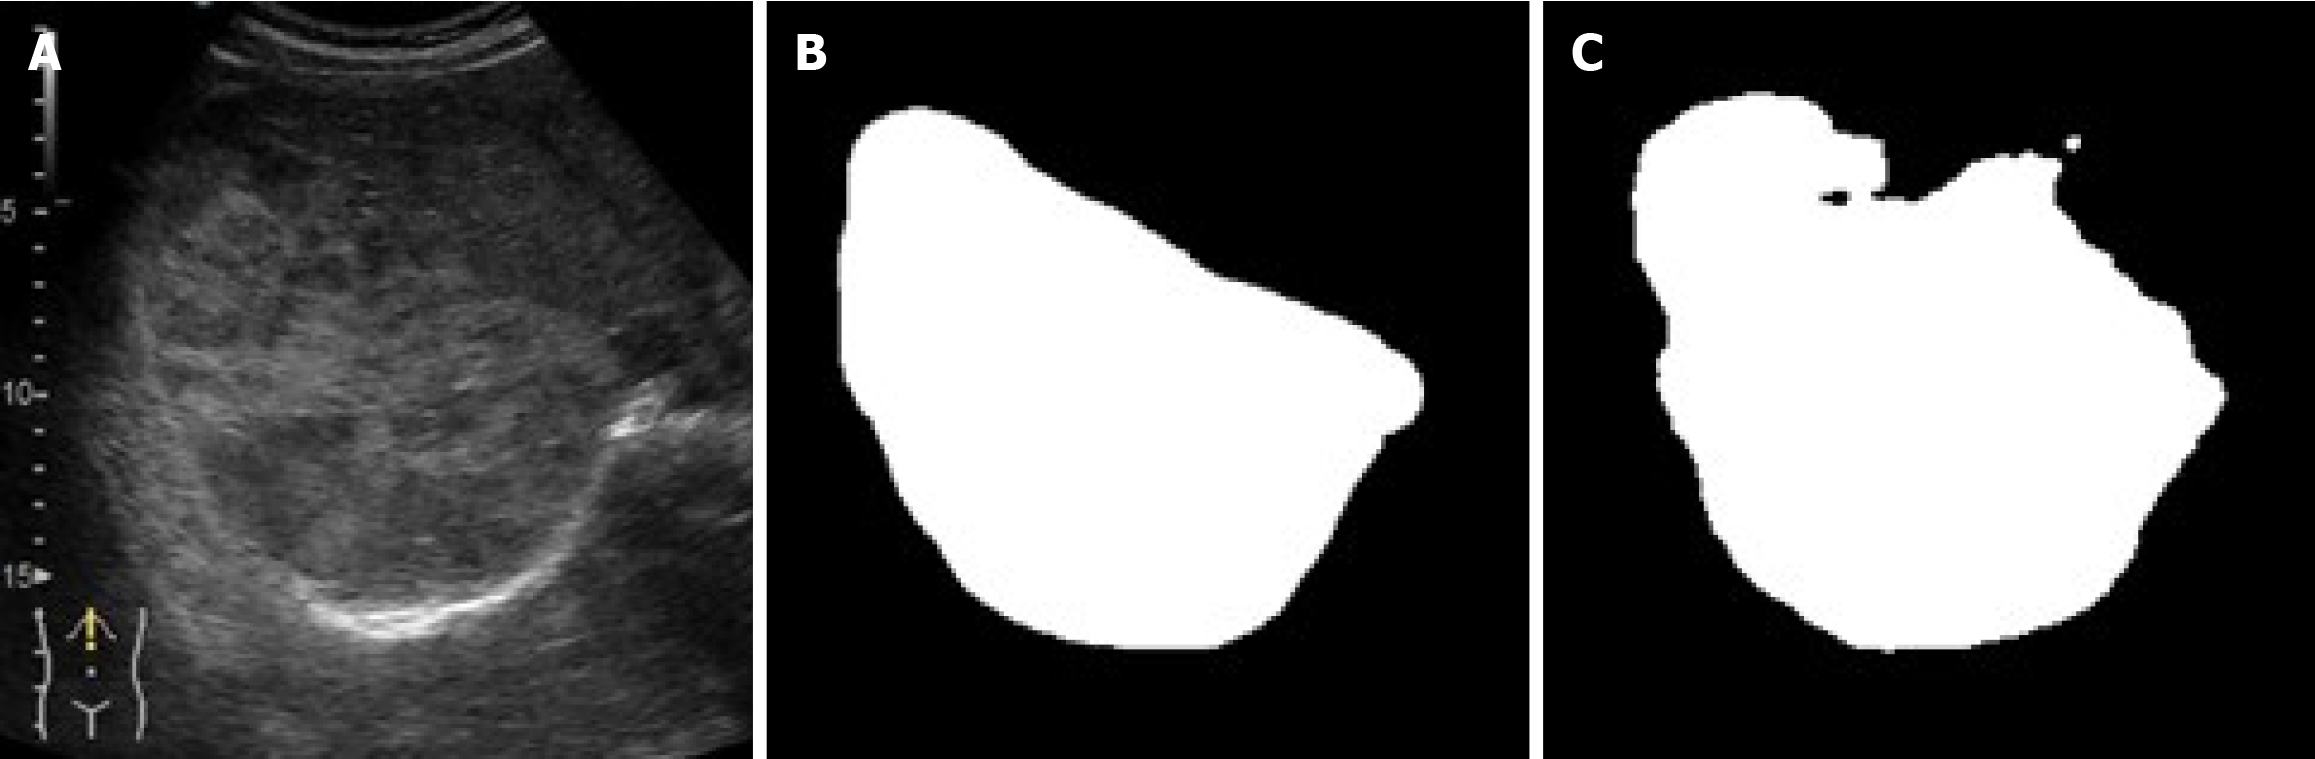

Figure 3 Expert annotation and artificial intelligence segmentation of a focal liver lesion on contrast-enhanced ultrasound.

A: B-mode image; B: Its corresponding mask defined by the expert physician (labeling phase).